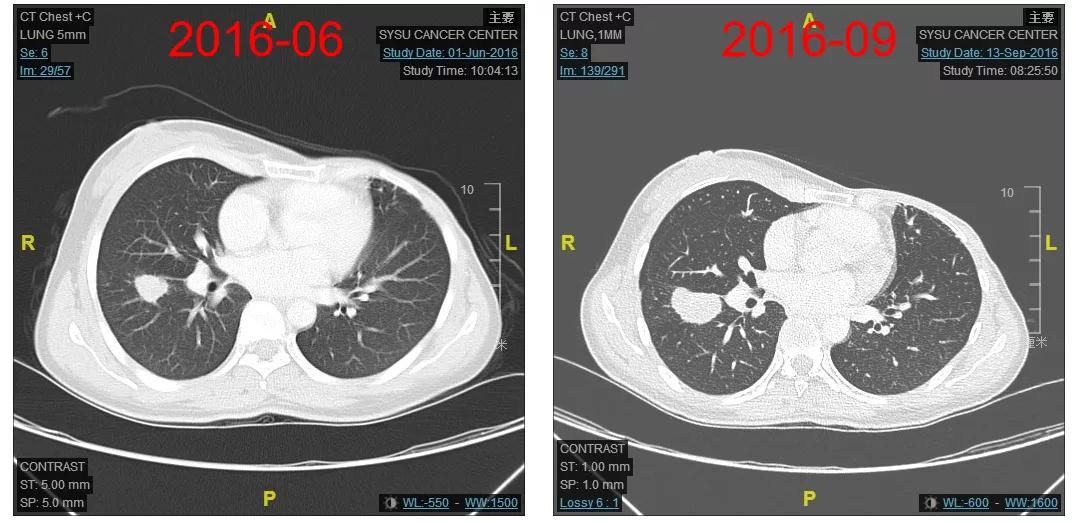

2016-06-01复查CT:右肺下叶上段团块状肿物(图1),考虑转移。

图1

2016-12-06开始使用T-DM1(恩美曲妥珠单抗)方案治疗,首次疗效评估PR,后续最佳疗效CR(图2-3)。